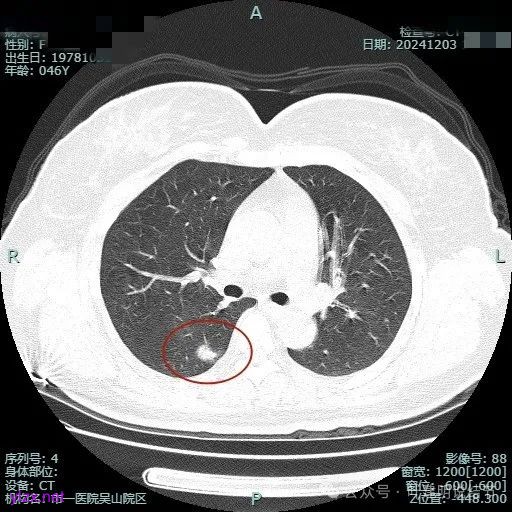

复查情况:

到了2024年12月复查,发现三处病灶均无明显好转,但也说不上明显进展。不过抗炎无好转,结核与隐球菌方面又无依据,那是多原发肺癌的可能性就大为增加了,而且跨叶生长说明侵袭性不小的,建议尽快再办理住院手续接受手术治疗。结友说回去再商量考虑下,结果一去不返。

时间很快到了2025年3月,结友又来我门诊复查,我还以为她在别处开了刀了呢,结果并没有,说是与家人商量后决定吃中药三个月看看能不能好。我们来看看再复查的情况,中药有没有起作用:

总体感觉三处病灶边缘的淡磨玻璃成分好转不太明显了,实性成分较前略显致密点,大小与形态是说不上显著变化的。所以有几点可以肯定:1、消炎没有效;2、中药没有用;3、考虑多原发肺癌,且为浸润性腺癌可能性大些,得手术!